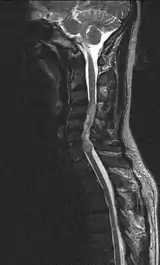

| Ependymoma of the cervical spine, completely obscurating the spinal canal |

Froin's syndrome – coexistence of xanthochromia, high protein level and marked coagulation of cerebrospinal fluid (CSF). It is caused by meningeal irritation (e.g. during spinal meningitis) and CSF flow blockage by tumour mass or abscess.[1] Stagnation of the CSF within the thecal sac facilitates exudation from the tumour itself and activation of coagulation factors. A clinical test formerly used for evaluation of spinal stenosis is Queckenstedt's maneuver. Nowadays, a magnetic resonance imaging is used for identification of CSF flow obstruction. It often shows the prolongation of T1 and T2 signal in CSF caudal to a level of block.[2] This phenomenon is named after Georges Froin (1874–1932), a French physician who first described it.[3][4]